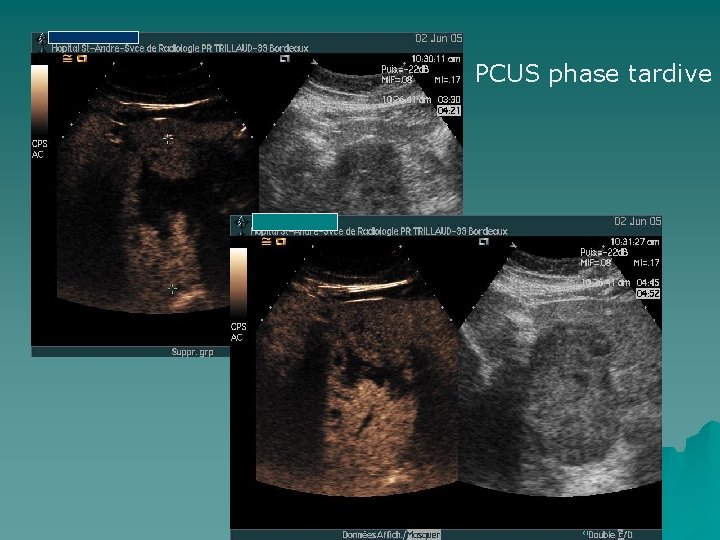

PCUS phase tardive

IRM hépatique Séquence pondérée en T 2 Phase art Phase port Phase tardive 1